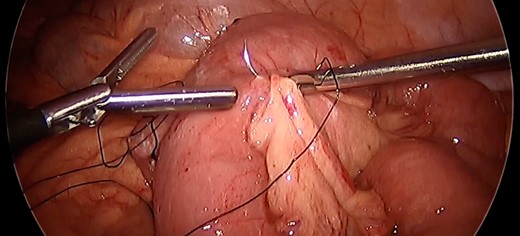

Given the propensity of the distal Roux limb to intussuscept into the enteroenterostomy, enteropexy was performed to eliminate its travel past the anastomosis. The distalmost aspect of the Roux limb was sutured with two pieces of running 3-0 silk to the end of the staple line on the biliopancreatic limb. Two additional sutures were placed slightly more upstream anchoring the roux limb to the mesentery of the transverse colon. An additional 3-0 silk suture was placed on the opposite side of the distal Roux limb anchoring it to the nearby mesenteric root. (Fig. 3) A 3–0 silk suture was placed to fix the common channel to the biliopancreatic limb to similarly limit the risk for intussusception of that limb. After this procedure, the small bowel was immobilized such that there was no longer predisposition for intussusception at the Roux-en-Y enteroenteric anastomosis (Fig. 4).

After enteropexy. Demonstration of nonabsorbable suture placement for enteropexy and subsequent inability to intussuscept the common limb into the enteroenteric anastomosis.